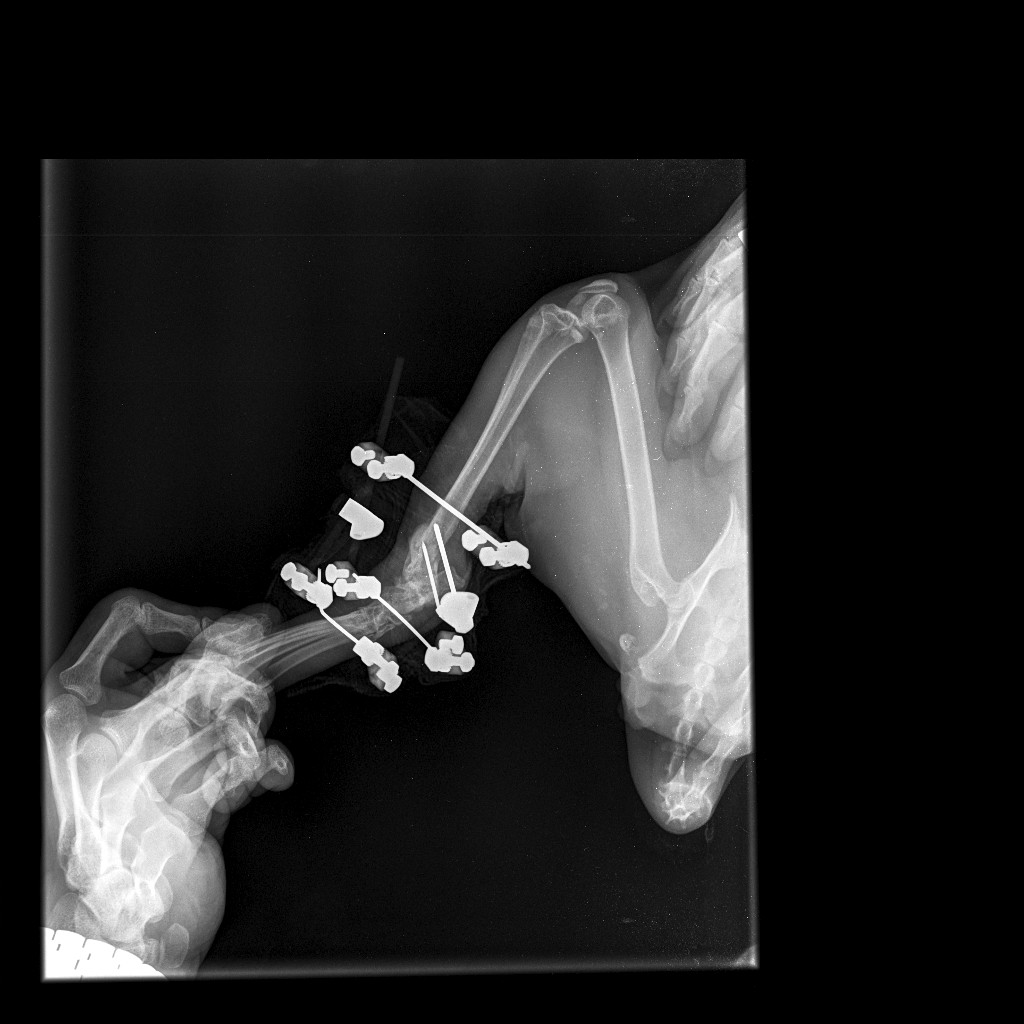

Добрый вечер, дайте свою оценку пожалуйста  у котика был сложный перелом ( упал с пятого этажа ) сделали операцию, поставили аппарат элизарово, по рекомендации врача кот всегда находится в клетке , на днях съездили на рентген где показал перелом  как могло это произойти ? операция стоила не маленьких денег , со своей стороны соблюдала все рекомендации и тут такое ( врач другой дал свою оценку и сказал , что возможно не правильно поставлен аппарат , на большой сустав одна спица а желательно две ( посмотрите пожалуйста снимки, так ли это ( как бороться с клиникой которая провела операцию ?!( на первом снимке после операции, на втором сделаны вчера .. так же фото лапы сегодня , нащупала два выступа и теперь думаю кость это или спицы вставлены там

Здравствуйте. По снимкам видно, что перелом был действительно сложный, с раздроблением костей. Аппарат Илизарова установлен, однако на одном из суставов действительно стоит только одна спица, тогда как обычно рекомендуется 2 для более устойчивой фиксации. Это могло сказаться на стабильности конструкции и привести к смещению. Выступы которые вы нащупали могут быть как края костных отломков, так и элементы спиц. Чтобы точно оценить  нужен очный осмотр и повторный рентген в динамике.